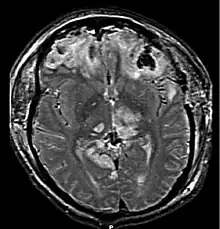

| Brain injury with herniation MRI |